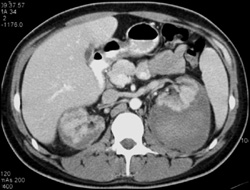

Diagnosis

Renal Infarcts With Narrowed Aortic Lumen and Clot in Renal Artery and Celiac Artery